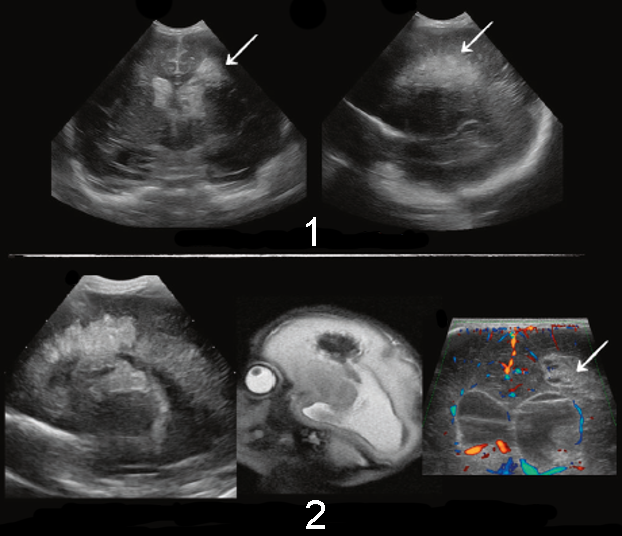

1. The top images show limited terminal vein area infarction

2. The bottom images show extensive anterior terminal vein area infarction (above caudate head)